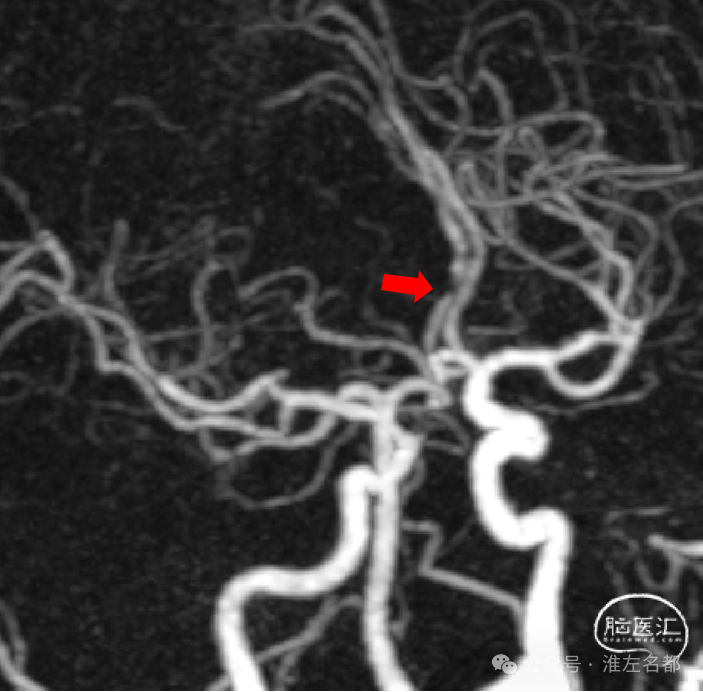

颅脑CTA:右侧大脑前动脉A2段局部管腔严重狭窄,右侧大脑前动脉A1段未发育,左侧大脑前动脉A1段粗大。

3D-TOF-MRA:右侧大脑前动脉A2段管腔未见明确异常。